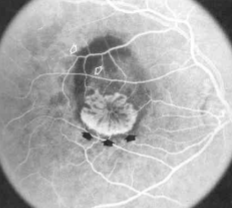

classic CNV/Gass type 2

CNVM

well defined hyperfluorescence

cartwheel or sea fan appearance

thought to break through RPE & staying sub-retinal

type 2 MNV

MNV is now b/t neurosensory retina & RPE making the IVFA more obvious & well defined

IVFA shows lacy, well-group area of neovascularization

hyperfluorescent early in study

late leakage

lacy early fill of the MNV during the choroidal & arterial filling phase

may have hypofluorescence corresponding to RPE hyperpigmentation & blood in the outline of the MNV

progressive hyperfluorescence throughout the FA w/o leakage of the margins of the MNV

classic CNV

classic & occult CNV

type 2 MNV

MNV type 2

MNV type 2

MNV type 2

MNV type 2

MNV type 2